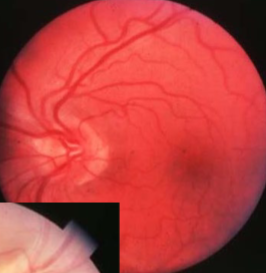

MNF